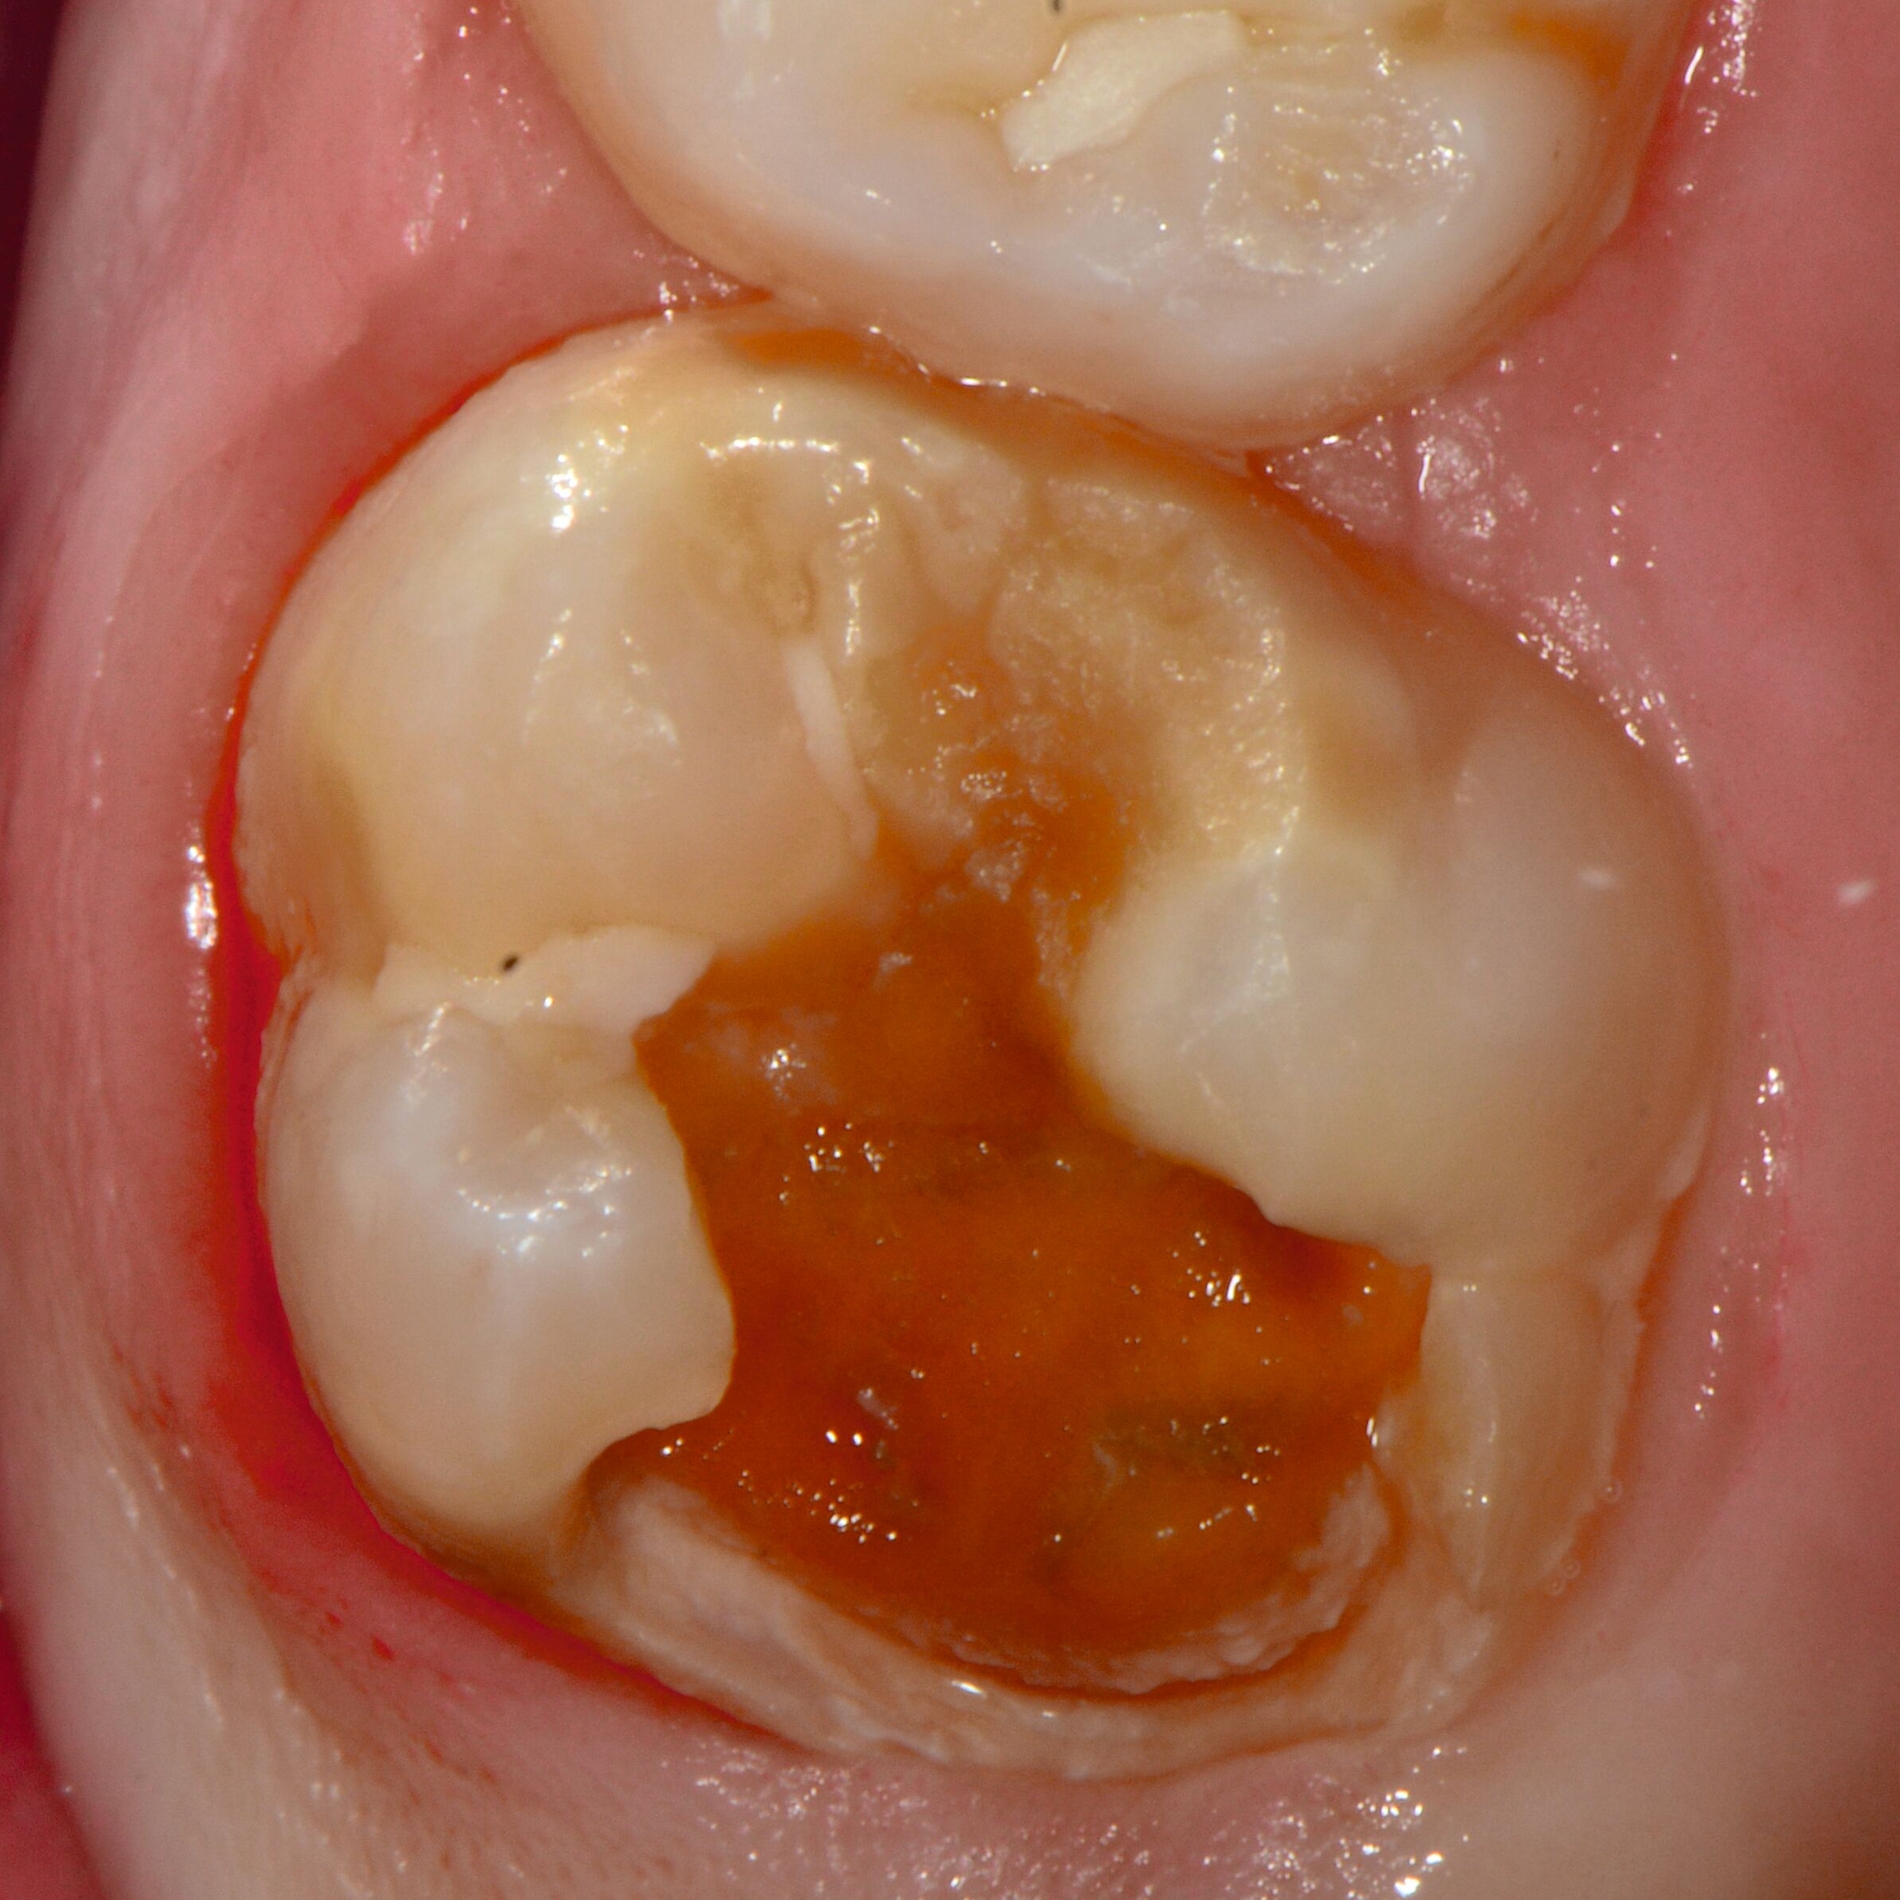

Bei post- beziehungsweise präeruptiven Oberflächendefekten ergibt sich in einigen Fällen die Indikation zur Restauration dieser MIH-Zähne. Unter Verweis auf die Lokalisation von MIH-bedingten Hypomineralisationen außerhalb der typischen Kariesprädilektionsstellen – zum Beispiel okklusale Fissuren und Grübchen oder Approximalflächen – werden diese als „atypische Restaurationen“ (engl.: „atypical restoration“, Abbildung 6) klassifiziert. Als ein weiteres Erkennungsmerkmal gilt die Präsenz von Hypomineralisationen im Bereich der Restaurationsränder. MIH- und kariesbedingte Restaurationen können und sollten sicher voneinander abgegrenzt werden.

Für die Dokumentation und Klassifikation der MIH wurden verschiedene Systeme vorgeschlagen. Als historisch und veraltet gilt der (modifizierte) DDE-Index. Demgegenüber haben die Kriterien der EAPD – abgegrenzte Opazitäten (Abbildung 3 und 4), Schmelzeinbrüche (Abbildung 5), atypische Restaurationen (Abbildung 6) – mittlerweile die weiteste Verbreitung gefunden. Diese wurden 2003 erstmals zur Beschreibung der MIH auf empirischer Basis publiziert [Weerheijm et al., 2003] und den Jahren 2010 und 2022 im Rahmen der damaligen MIH-Workshops bestätigt [Lygidakis et al., 2010; 2022].